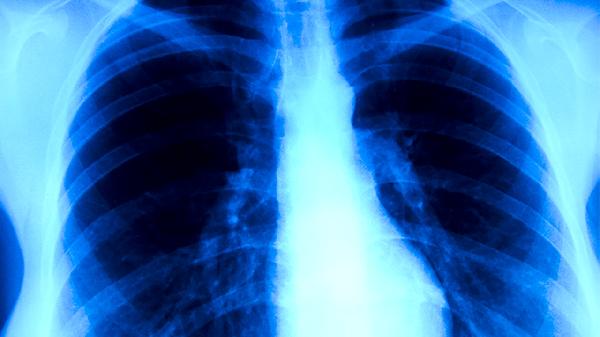

肺结核治疗需遵医嘱联合使用抗结核药物,常用方案包括异烟肼片、利福平胶囊、吡嗪酰胺片、乙胺丁醇片和链霉素注射液等。肺结核是由结核分枝杆菌引起的慢性传染病,需规范用药6-9个月。

肺结核患者除规范用药外,需保持充足营养摄入,适当补充优质蛋白和维生素。治疗期间应单独居住并保持室内通风,咳嗽时遮掩口鼻。定期复查胸部影像学和痰菌检查,全程不得擅自停药。出现药物不良反应应及时就医调整方案,耐药结核病患者需接受二线药物治疗18-24个月。完成疗程后仍需随访2年以防复发。